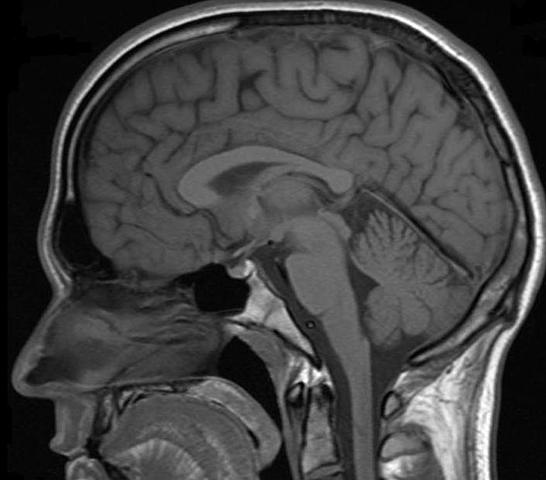

• Imagenes de Resonancia Magnetica

Imagenes de Resonancia Magnetica

Paul Lauterbur desarrolla la forma de generar las primeras imágenes de resonancia magnética (MRI) bidimensionales y tridimensionales. En este año publicó la primera imagen de resonancia magnética nuclear.